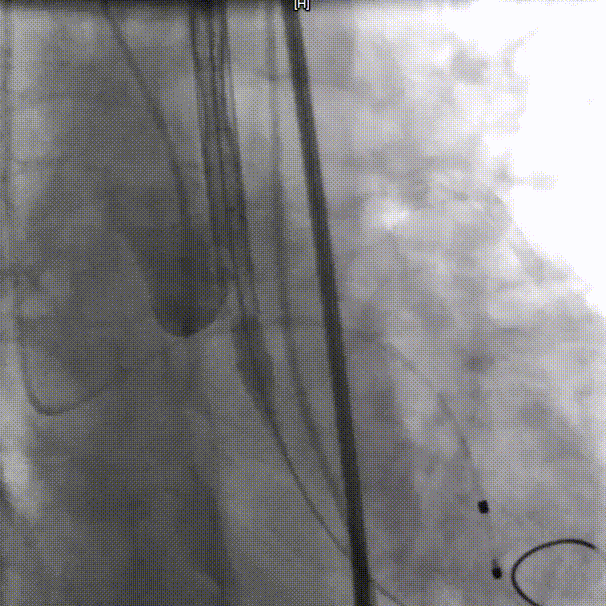

手术过程概览

整体入路造影,右侧细,走左侧为主入路,左侧用外周球囊预扩后送大鞘

术前压差163mmHg

20mm球囊预扩,球囊下滑

再次预扩,球囊上跳

瓣下3mm定位

释放到工作位,瓣下5mm左右

缓慢脱钩

左冠窦侧微量反流

22mm球囊后扩

患者压差从163mmHg降为6mmHg,效果显著。